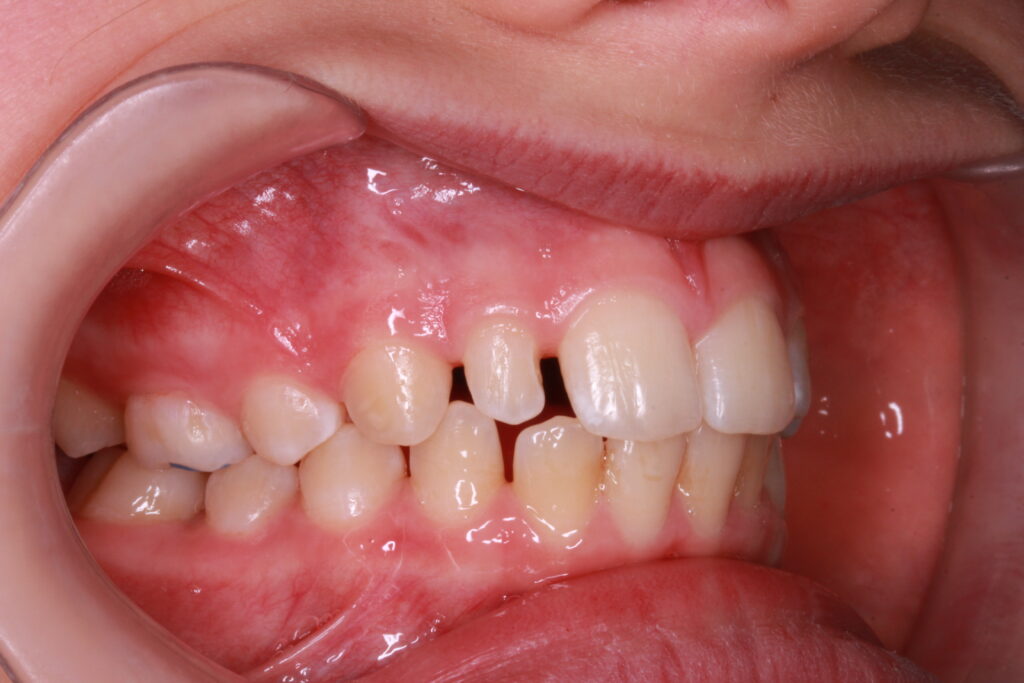

✔ Class II, Class III, aszimmetria és keresztharapás elméleti megközelítése

Az ALF készülék nem az agresszív erőhatásokra, hanem a funkcionális erők finom, biológiailag kíméletes irányítására épít. A klinikai tapasztalatok szerint ez tökéletes elég és mind a fogív fejlesztésében, keresztharapások megszűntetésében, helyteremtésben mind a nyelvtér növelésében jól működik.